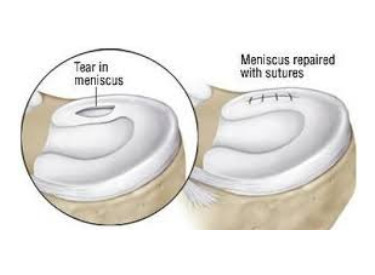

- 2. Lesiones de menisco: Los meniscos son cartílagos en forma de media luna ubicados en la rodilla. Si se produce una rotura en el menisco, es posible que se requiera una cirugía para reparar o extirpar la parte dañada.